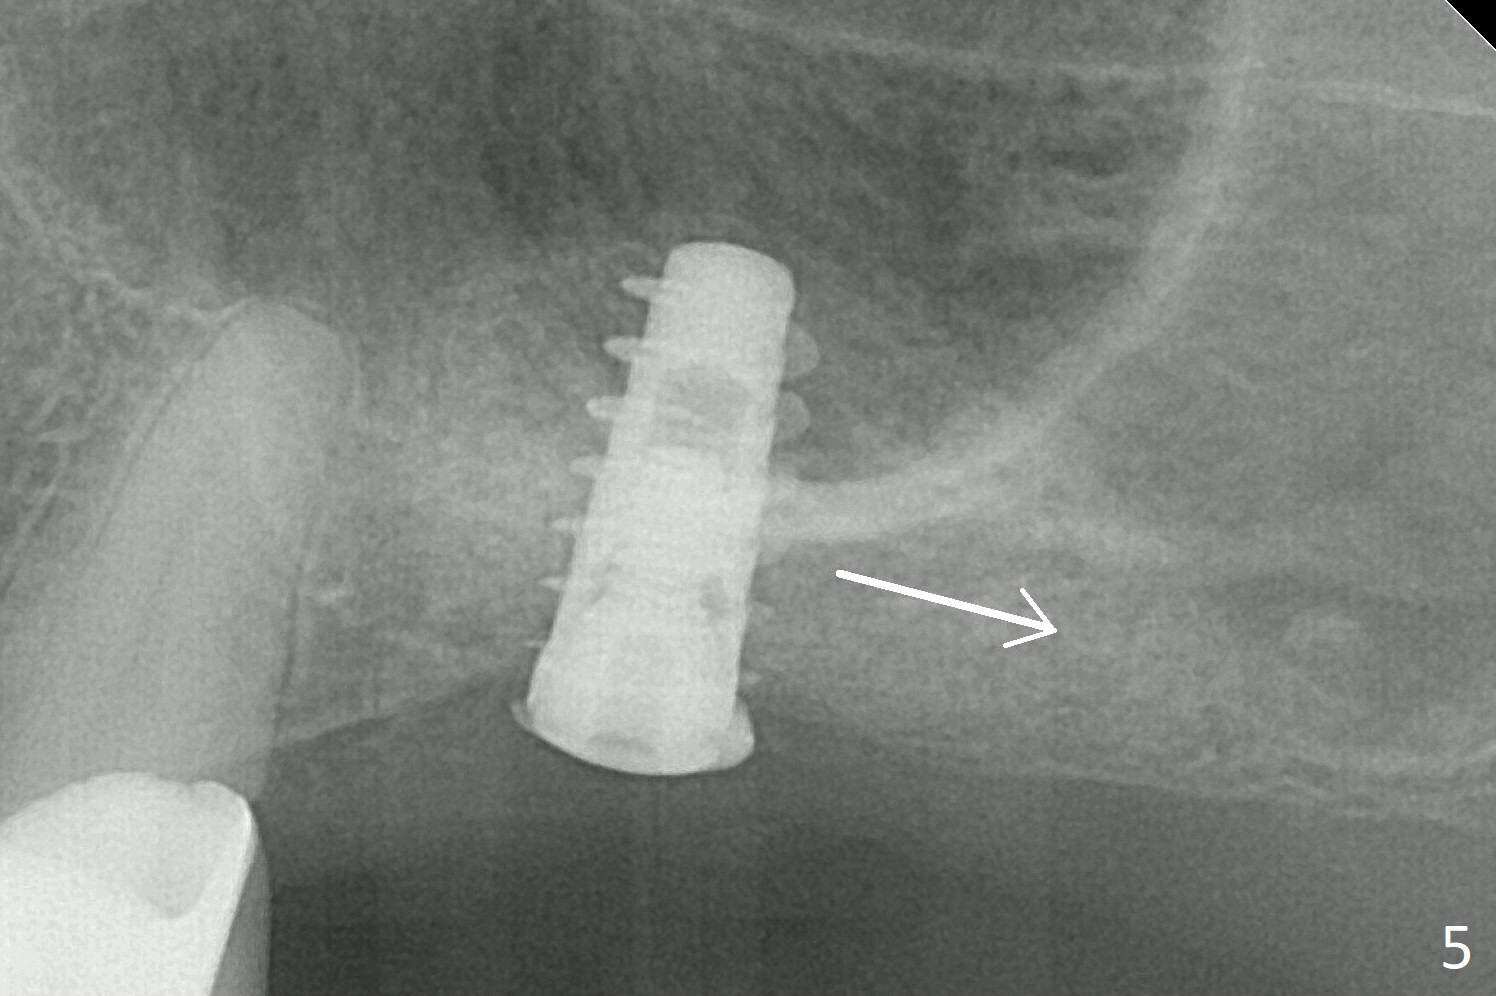

Magic Sinus Lifter is used to elevate the sinus floor for ~ 5 mm, followed by insertion of allograft/Osteogen and 4.0x11 mm dummy implant partially (Fig.1). With approximately 10% more of graft being placed, a 4.5x9 mm IBS implant is placed with insertion torque of 15 Ncm (Fig.2). The implant has a tenting effect. The bone graft appears to move distal 1 month 20 days postop (Fig.5 arrow), while the implant seems to be extruded with implant exposure. The patient feels pain when the healing screw is being removed or tightened. The distal migration of the bone graft may lay foundation for future implant placement at #15. Can the implant at #14 be retorqued to be seated deeper 3-4 months later? Bone density around the implant remains the same (Fig.6), while the wound reduces nearly 3.5 months postop (Fig.7). There are two layers of the bone, one (1) being denser than the other (2) 8 months postop (Fig.8). After local anesthesia, the healing screw is removed; the implant is found to be stable. A 6x4(2) mm pair abutment cannot be inserted due to blockage of the mesiobuccal gingiva (Fig.9 *). Instead a 6x2 mm healing abutment is placed. Three weeks later (approximately 8.5 months postop), the implant is found to be able to rotate when a 6.5x5.7(1) mm pair abutment is tightened with local anesthesia (there is pain associated with healing screw removal). After removal of the latter, the implant is placed deeper by hand retightening (Fig.10 arrow). Is it a better idea to use a new larger implant instead? The patient (53 years old) is scheduled to return for follow up in 3 months.